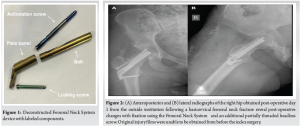

Femoral neck fractures in young adults only comprise 2–3% of all femoral neck fractures and often result from high-energy trauma [1]. Studies have shown an association between these fractures in young adults and high incidences of osteonecrosis and non-union [2-7]. Fixation strategies in young patients emphasize anatomic reduction, preserving blood supply, and stable fixation to reduce complications. Classic fixation methods include closed reduction and percutaneous pinning (CRPP) with cannulated screws and sliding hip screw (SHS). Complication rates after CRPP and SHS remain high, with studies showing the incidence of osteonecrosis at 14.3%, malunion at 7.1%, and implant failure at 9.7%, with complications correlated with increasing Pauwel’s angle [8]. The Femoral Neck System™ (FNS) (Fig. 1) is a fixation device that aims to reduce varus collapse risk, increase mechanical and rotational stability compared to CRPP, and decrease incision size and incidence of lateral thigh pain compared to SHS [9-12]. While the FNS aims to combine the benefits of CRPP and SHS while eliminating the challenges associated with each, reported outcomes from in vivo studies are limited. Recent meta-analyses comparing the FNS to other fixation strategies have reported favorable union rates and relatively low complication rates, including rare instances of implant failure. However, few reports have detailed the specific modes of failure or the intraoperative challenges that may arise during revision surgery [13,14]. We report a case of FNS implant failure in a young patient with a femoral neck fracture occurring within 1 year of surgery. The patient consented to the publication of her case.